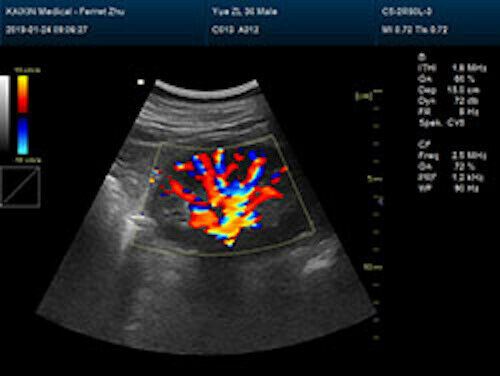

Large Animal Veterinary Color Doppler Ultrasound & Rectal Probe

| Powerful function & Configuration • Large screen display • Built-in lithium battery • Small size, light weight, easy to carry, N.W. ≤ 5kg • Equipped with a wide range of probes for abdominal, obstetric, vascular, cardiac, small organ, urinary applications • Built-in 4D module with optional 4D volume probe • A variety of digital peripheral interfaces, provides a variety of image output methods • PC platform, easy to operate, meet various software upgrades |

| Rich clinical application function • B+CF (Dual Images) • B+CF/PDI/DPDI+PW (Triplex) • Convex extended imaging technology • Linear array deflection/Trapezoidal imaging technology • Spatial compound Imaging technology • Panoramic imaging technology (optional) • 3D/4D imaging technology (optional) • Speckle noise removal technology • Pulse inversion tissue harmonic imaging technology (iTHI) |